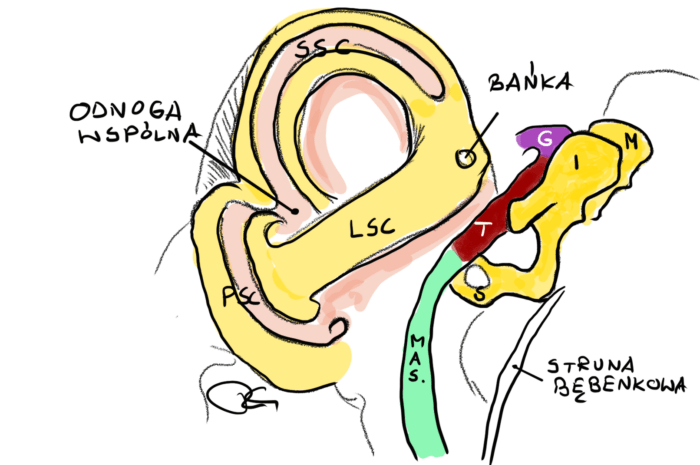

- Podział nerwu twarzowego na segmenty ze szczegółowym opisem ich topografii (przy okazji sporo będzie informacji na temat budowy ucha)

- Jakie gałęzie odchodzą lub dochodzą do nerwu twarzowego w poszczególnych segmentach

- Podział nerwu twarzowego na segmenty ze szczegółowym opisem ich topografii (przy okazji sporo będzie informacji na temat budowy ucha)

- Jakie gałęzie odchodzą lub dochodzą do nerwu twarzowego w poszczególnych segmentach